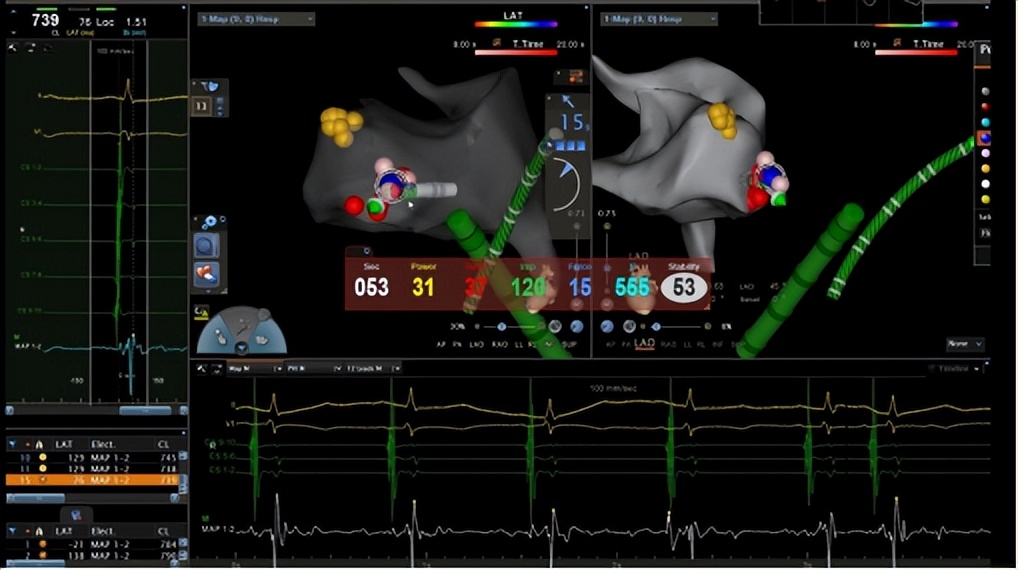

手术的关键,是找到心脏里的“异常激动点”。郑全主任团队通过股动脉送入射频导管,在三维导航仪指引下,在心脏主动脉瓣二尖瓣连接处(AMC区域)精准定位。

△术中三维导航,确定异常病灶,治疗快速性心律失常